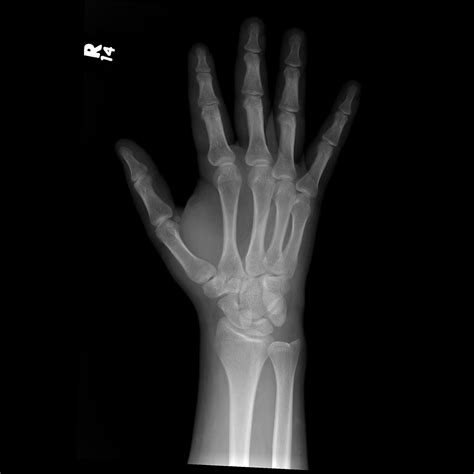

Diagnosing a stress fracture wrist involves a combination of physical examination and imaging tests. The diagnostic process typically includes:

• Imaging Tests: X-rays, MRI, or bone scans may be ordered to visualize the fracture and determine its severity.

Imaging tests are particularly important because stress fractures may not be visible on initial X-rays. An MRI or bone scan can provide a more detailed view of the bone structure and help confirm the diagnosis.